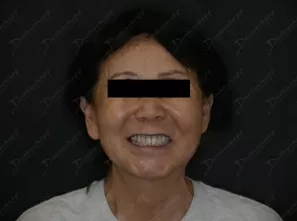

Фото работ